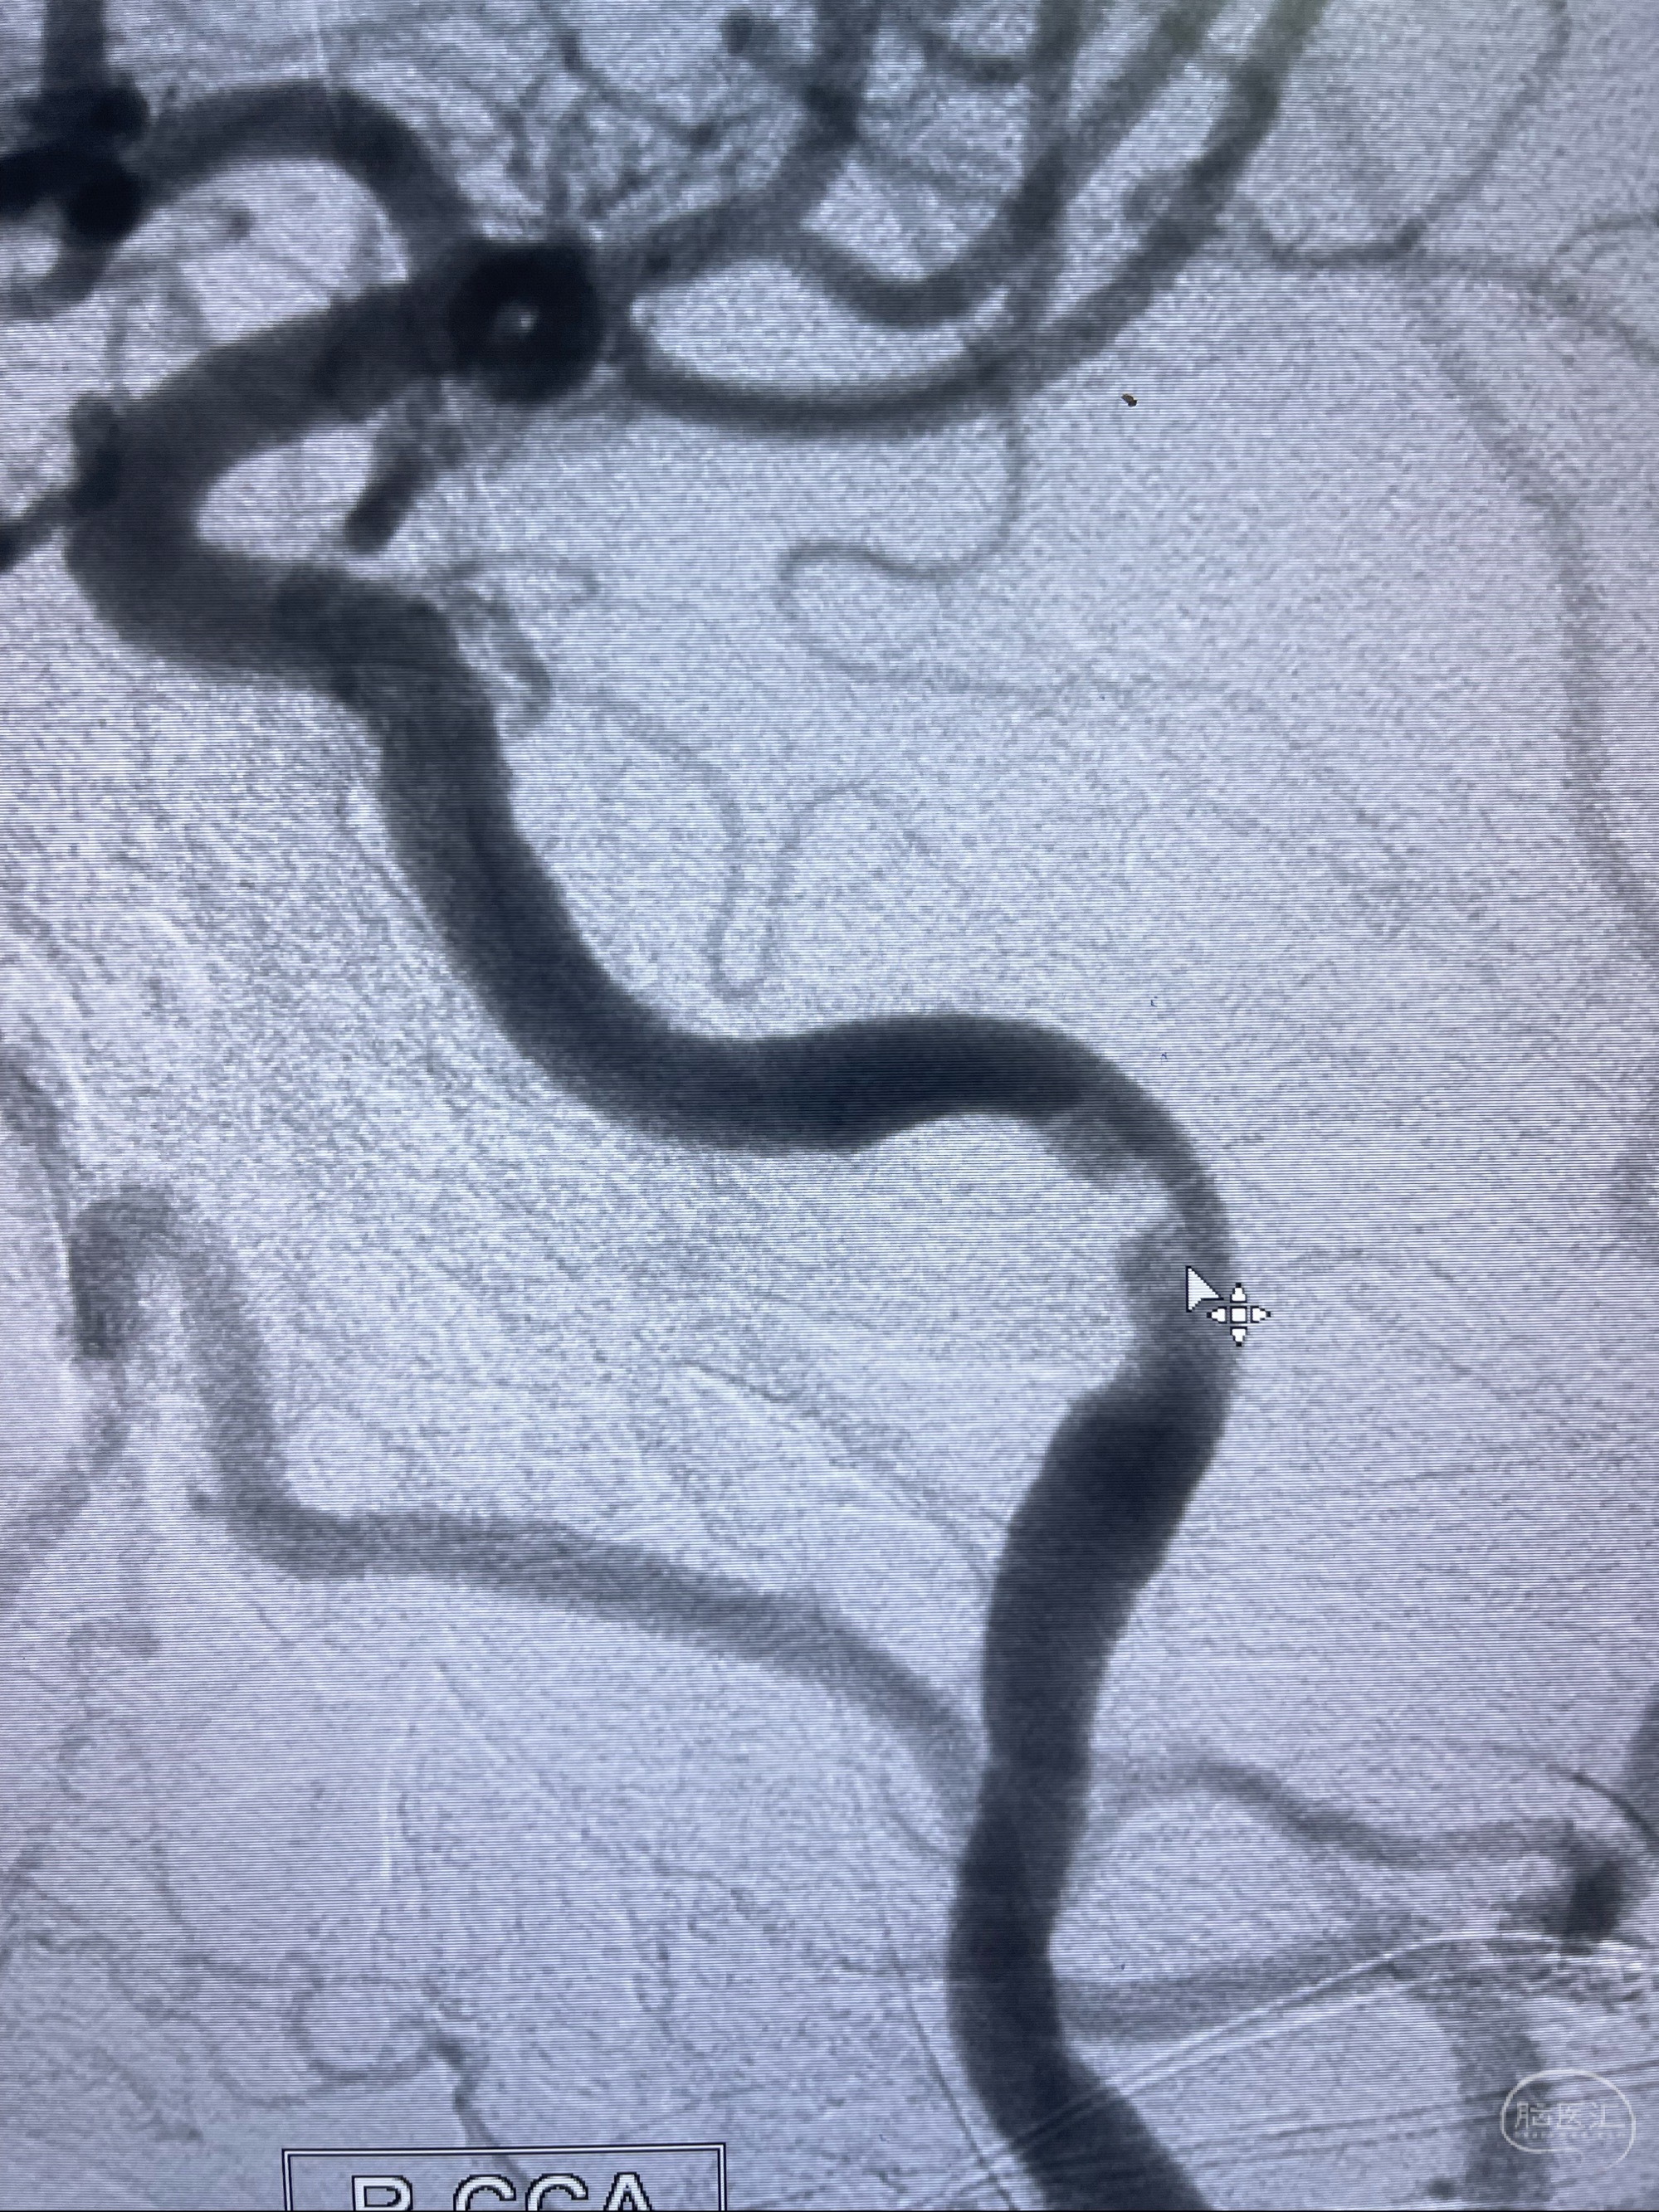

2023-07-10DSA:右侧颈内动脉岩骨段夹层伴中偏重度狭窄改变,左侧颈总动脉闭塞、右侧颈外动脉由右侧肋颈干甲颈干吻合代偿

箭头所示为颈内动脉岩骨段重度狭窄,结合MRI,考虑为肿瘤侵犯右侧颈内动脉

箭头以近至支架段管腔不规则狭窄